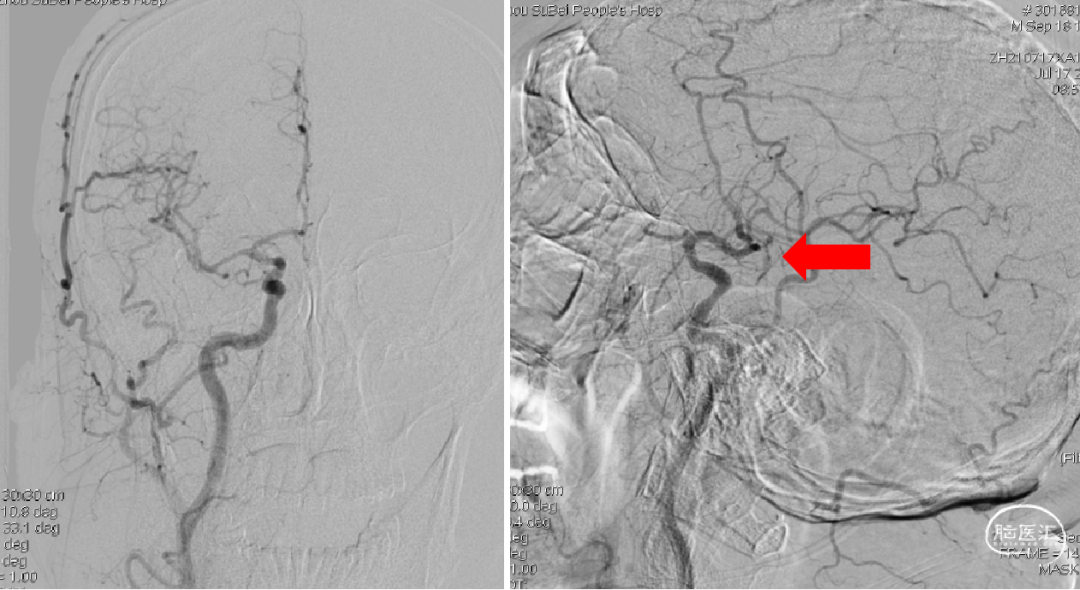

1、考虑右侧椎动脉V4段闭塞,不再犹豫,即刻选择左侧椎动脉入路;2、左侧椎动脉造影:提示V4段末端瘤样扩张伴基底动脉近端重度狭窄。

ACE60抽吸导管+RECO 4×20mm取栓支架抽拉结合,造影示基底动脉近端重度狭窄,远端通畅。

1、取栓两次,第二次将尼科支架置于狭窄处;2、第二次取栓后造影基底动脉近端重度狭窄,远端通畅。

1、术后即刻造影;2、15分钟后再次造影,基底动脉近端仍有重度狭窄,远端血流稀疏、缓慢。

1、选择2×15mm球囊针对狭窄处进行亚满意扩张;2、术后造影,狭窄好转,远端血流明显改善,观察15分钟后未见明显变化后结束手术。